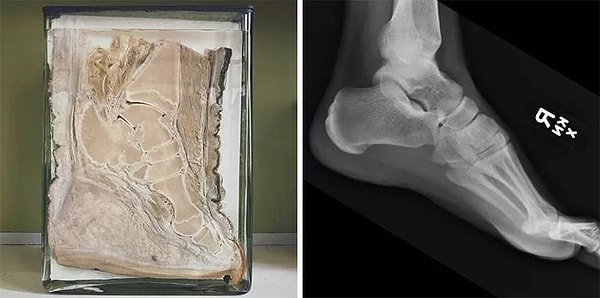

11. Нога слона в сравнении с ногой человека.